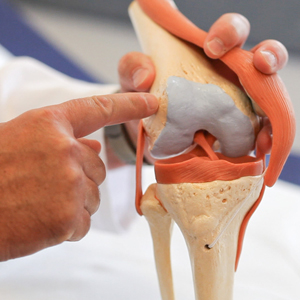

Knie

Das Kniegelenk ist das größte Gelenk im menschlichen Körper. Bestehend aus drei Gelenkanteilen verbindet es den Oberschenkelknochen mit dem Schienbeinknochen, an deren Enden sich jeweils eine dicke, glatte Knorpelschicht befindet. Die dazwischen liegenden Faserknorpelscheiben – der Innen- und Außenmeniskus – passen sich jeder Bewegung an und dienen als Stoßdämpfer für die zahlreichen Druck-, Zug- und Beschleunigungskräfte, denen das Knie jeden Tag ausgesetzt ist.

Bild Orthopädie Kniemodell